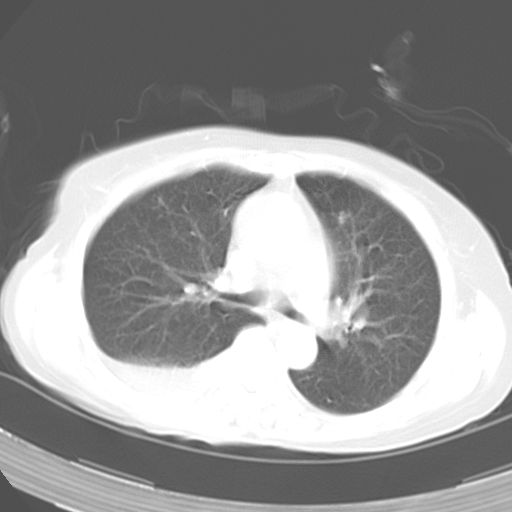

以下是引用dyqct在2006-12-7 21:08:00的发言:[br]考虑:1、肝内外胆管多发性结石伴肝左叶外侧段肝萎缩;[br] 2、右膈下多发脓肿;[br] 3、右侧少量胸腔积液、斜裂积液;[br] 4、左肾囊肿。

以下是引用jiazh在2006-12-7 20:37:00的发言:[br]肝脏周围半狐形低密度影,肝脏表面受压推移,考虑膈下脓肿可能性大;2、右侧胸腔积液

以下是引用拾荒者在2006-12-7 21:44:00的发言:[br]肝内外胆管多发结石,右膈下多发脓肿,右胸膜腔及叶间裂积液,左肾囊肿。[br] [br]